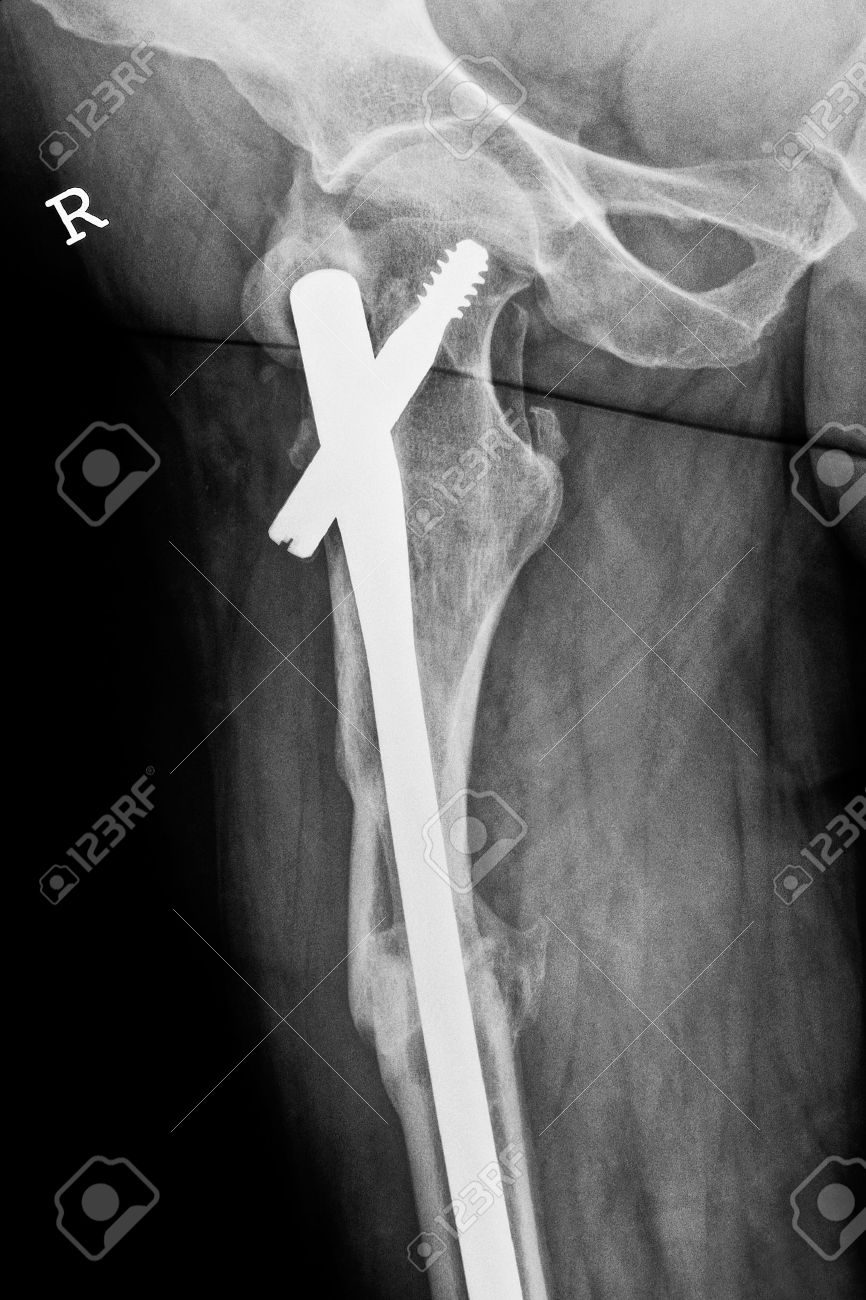

» Long gamma nail (97) 사진

Long gamma nail (97) 사진